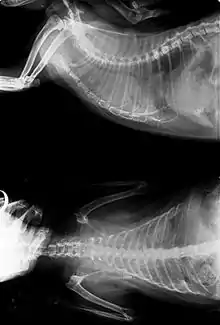

- X-rays may or may not make use of contrast techniques to help visualize the gastrointestinal tract. They are commonly used to identify tumors of the lung, gastrointestinal tract and bladder.